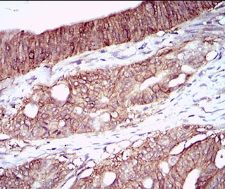

CA9 Mouse Monoclonal antibody[7C4A5]

Carbonic anhydrases (CAs) are a large family of zinc metalloenzymes that catalyze the reversible hydration of carbon dioxide. They participate in a variety of biological processes, including respiration, calcification, acid-base balance, bone resorption, and the formation of aqueous humor, cerebrospinal fluid, saliva, and gastric acid. They show extensive diversity in tissue distribution and in their subcellular localization. CA IX is a transmembrane protein and the only tumor-associated carbonic anhydrase isoenzyme known. It is expressed in all clear-cell renal cell carcinoma, but is not detected in normal kidney or most other normal tissues. It may be involved in cell proliferation and transformation. This gene was mapped to 17q21.2 by fluorescence in situ hybridization, however, radiation hybrid mapping localized it to 9p13-p12.

IHC    1/200 - 1/1000